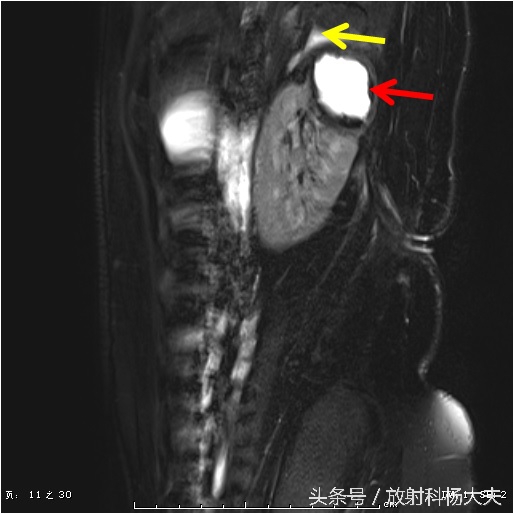

终于搞清楚了,原来一个月前的腰痛,是肾脏的脓肿,而且MRI上还能清晰的显示脓肿破口的位置,下图中黄箭所示(红箭为脓肿)。

还有那弯曲的窦道。